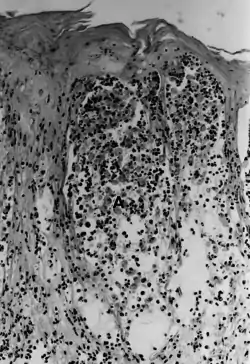

![]() Ящур — акантоліз у пробі шкірного пухирця: спостерігається некроз остистого шару надшкір'я, а кератиноцити плавають у пухирцевій рідині. Ящур — акантоліз у пробі шкірного пухирця: спостерігається некроз остистого шару надшкір'я, а кератиноцити плавають у пухирцевій рідині. | |